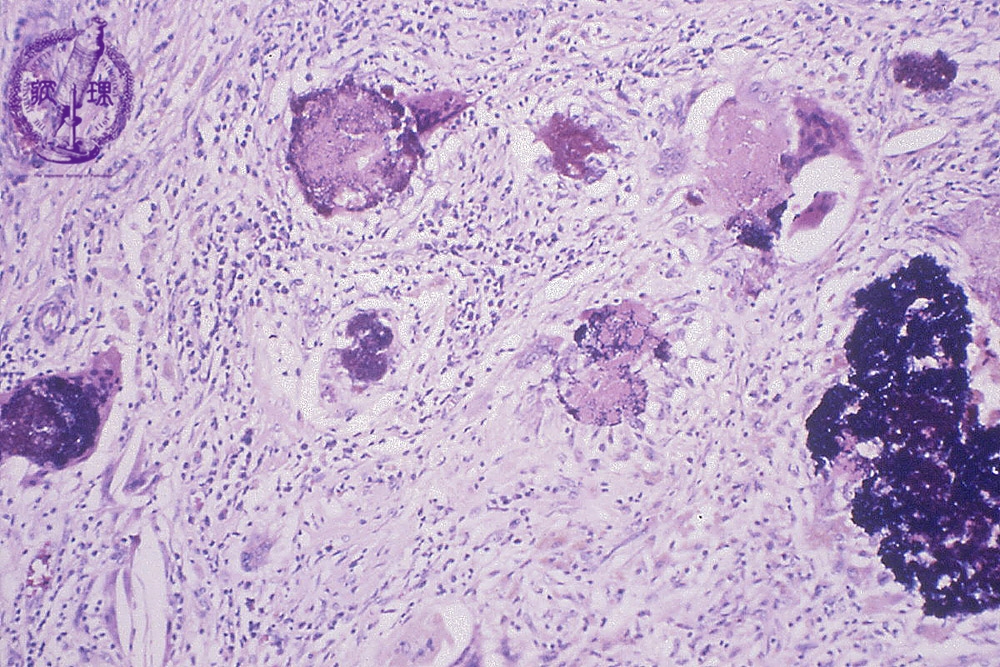

当院での症例のご紹介 みなみ野動物病院 八王子みなみ野。

Case50 試験開腹で反応性肉芽組織と診断された腹腔内腫瘤の犬の1例 –つつじヶ丘動物病院東京都調布市の動物総合病院。一般診療、循環器科、腫瘍科など。

Case50 試験開腹で反応性肉芽組織と診断された腹腔内腫瘤の犬の1例 –つつじヶ丘動物病院東京都調布市の動物総合病院。一般診療、循環器科、腫瘍科など。

えぬくりブログ: 毛細血管拡張性肉芽腫 化膿性肉芽腫。

血管拡張性肉芽腫の治療芳仁皮膚科医院院長 張賢二のブログ。